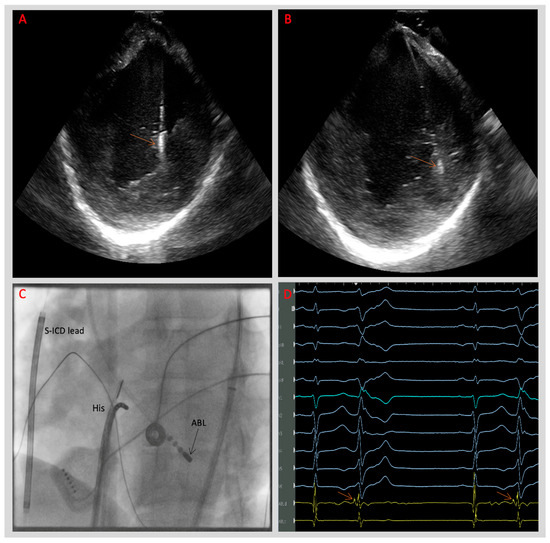

5.3. Catheter Ablation

5.4. Outcomes of Catheter Ablation